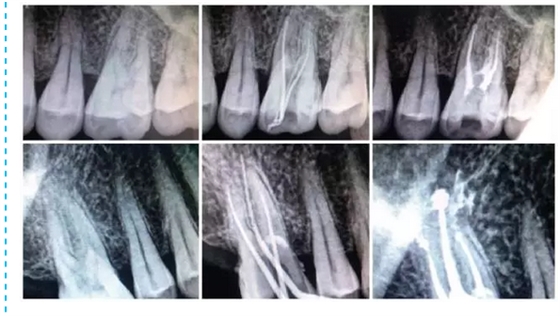

在臨床中選擇使用MM1500音波手機(jī)的基本步驟:選擇病例,急、慢性牙髓炎,根尖周炎,根管無鈣化,或鈣化根管已疏通,根管無明顯彎曲者。常規(guī)開髓,拔髓。使用手用器械大錐度鎳鈦銼去除根管口牙本質(zhì)領(lǐng),使用10號或15號銼針用根管長度測量儀測長,并插入擴(kuò)大針X線根尖片定位。按操作要求,將MM1500音波手機(jī)與牙科綜合治療臺上渦輪機(jī)工作端相連接,附帶的內(nèi)置式?jīng)_洗裝置使用蒸餾水,氣動壓力為30kPa,功率設(shè)置根據(jù)Rispisonic銼針磨損程度,從低檔至中檔選擇,設(shè)置工作長度,預(yù)彎銼針。以15號銼針開始預(yù)備,始終保持銼針在根管內(nèi)有一定的松動空間,與根管壁輕度接觸,并沿根管長軸提拉,幅度1~2 mm,待銼針可以在根管中較自由進(jìn)出時(shí),以大一號的手用器械K型銼行標(biāo)準(zhǔn)法修形后換同號的Rispisonic銼針,同法預(yù)備至所要求的號數(shù)。每更換一次器械均用新鮮配制2.5 g/L次氯酸鈉溶液沖洗根管,并要求每個(gè)根管至少預(yù)備到比初始號大兩個(gè)號以上。預(yù)備過程中用170g/LEDTA 液和125g/L 次氯酸鈉液交替沖洗根管。預(yù)備后,兩組均用氫氧化鈣糊劑行根管封藥消毒,一周后復(fù)診, 符合根充條件,即行根管充填。試尖合適,采用標(biāo)準(zhǔn)牙膠尖和AH-Plus 根管封閉劑側(cè)向加壓充填法充填根管。根管充填后行常規(guī)X線檢查。改換修復(fù)科進(jìn)行修復(fù)治療。